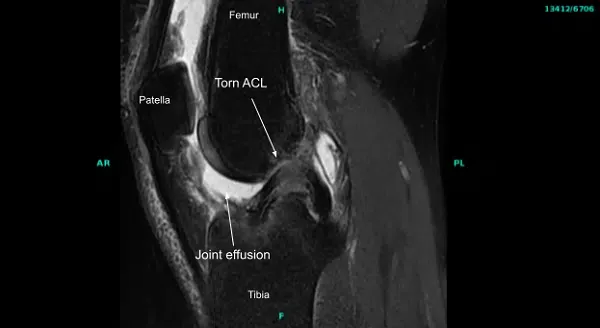

El examen físico dio positivo para deficiencia del LCA en la rodilla derecha. Las resonancias magnéticas de la articulación de la rodilla derecha confirmaron la lesión del LCA. No se detectó ninguna otra patología. El paciente había probado fisioterapia en el pasado sin ningún beneficio.

La extremidad inferior derecha se preparó y se colocó de forma aséptica de la manera habitual tras la aplicación del torniquete. Se administraron antibióticos preoperatorios. El torniquete se elevó tras Esmarch. El examen bajo anestesia mostró laxitud del LCA con un final blando, lo que coincidió con la resonancia magnética que encontró ausencia del LCA.